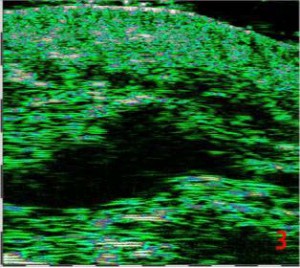

-Μέθοδοι θεραπείας υψηλής ενέργειας

(λέιζερ, RF-Ραδιοσυχνότητα, HIFU-Υψηλής Έντασης Εστιασμένος Υπέρηχος, κ.λπ.)